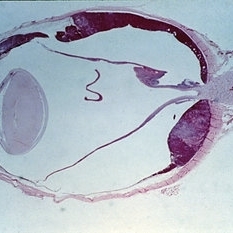

Among the objective manifestations of a choroidal melanoma, the most important is the presence of a solid mass seen on ophthaloscopic presentation. (seen in Slides 14-1 to 14-13). The shape and projection of the tumor can be best appreciated by observation with the indirect ophthalmoscope. The appearance of these tumors is typically that of a mushroom-shaped, collar button-shaped mass.

Condition/keywords: melanoma, tumor